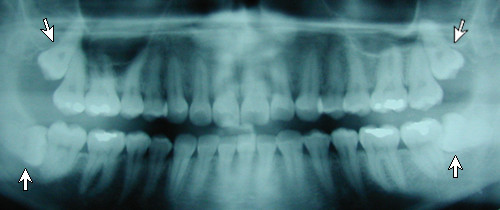

Panoramic x-ray of impacted teeth

This panoramic x-ray shows the impacted 3rd molars (wisdom teeth).

The upper wisdom teeth are crowding the sinus cavity and may erode the roots of the 2nd molars. The lower wisdom teeth are impacted sideways and are likely to cause crowding of the lower teeth, leading to malocclusion.